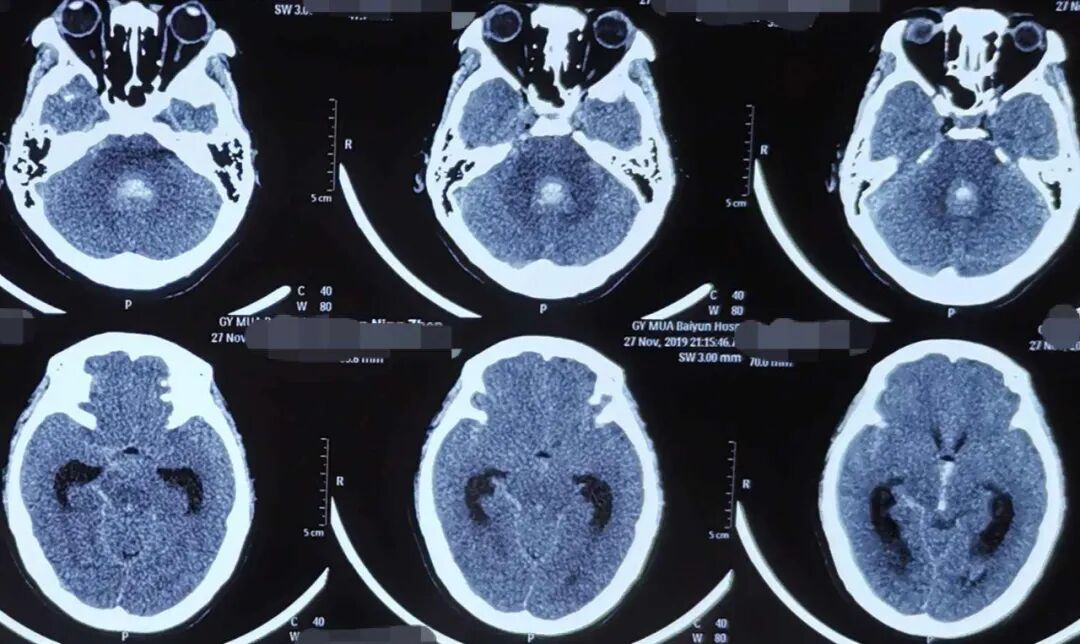

头颅 CT平扫

蛛网膜下腔出血病死率很高,应该尽快行脑血管检查,以明确病因,及时治疗。

CT可发现脑池和脑沟内的高密度影,有时脑室也有高密度出血影。

突发剧烈头痛,并伴有恶心、呕吐、意识障碍、癫、脑膜刺激征阳性及头颅CT检查发现蛛网膜下腔呈高密度影,即可确诊蛛网膜下腔出血。

若头痛不严重,脑膜刺激征不明显,头颅CT检查未发现异常,但仍怀疑蛛网膜下腔出血,则尽早行腰椎穿刺检查,腰椎穿刺结果提示为均匀血性脑脊液,亦可确诊蛛网膜下腔出血。